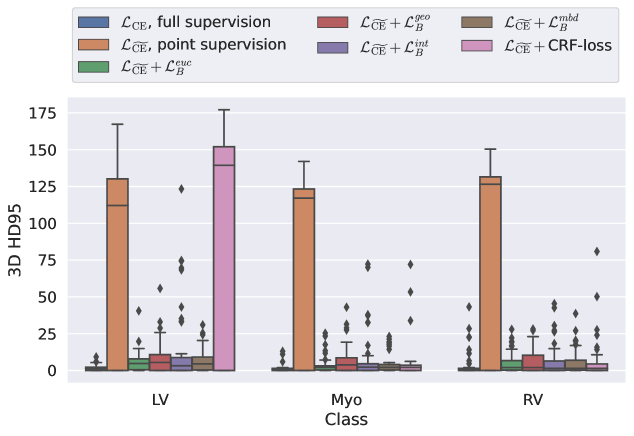

5.1 Segmentation of cardiac structures

The average 3D Dice scores and HD95 values on the ACDC test set are given in Table 2, and boxplots in figures 4 and 5 show the distributions. We see that, in terms of DSC, the proposed strategy of using intensity-aware distances withing boundary loss performs better than simply using the Euclidean distance, with the best results achieved by using the strictly intensity based MBD. The HD95 however favors the original version of , which may be do to its smoother predictions and less fragmentation and oversegmentation. The CRF-loss results are significantly worse in both metrics.

LABEL:\pgfplotslegendfromnamecommon

| Method | RV | Myo | LV | All |

|---|---|---|---|---|

| (fully supervised) | ||||

| (point annotations) | ||||

| w/ CRF-loss [33] |